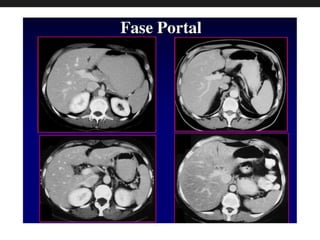

Fase Portal

• Fase intermediária de contrastação, com maior

opacificação do sistema portal. O mesmo

planejamento na fase arterial é repetido,

adquirindo-se os cortes entre 60 e 70 do início do

contraste. Neste momento, torna-se evidente o

contraste do sistema portal.